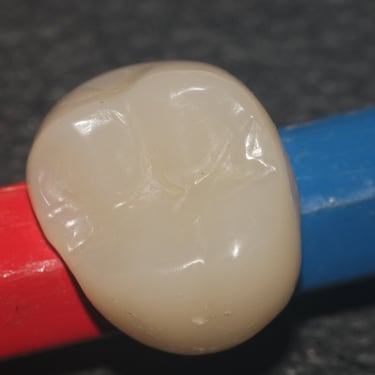

Dentes de porcelana finalizados